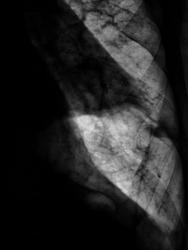

Произведено дообследование.

Рентгенография и томография.

Осумкованный пристеночный плеврит.

Пропунктировали, согласились "на осумкованный плеврит".

Похоже на осумкованный, или как?